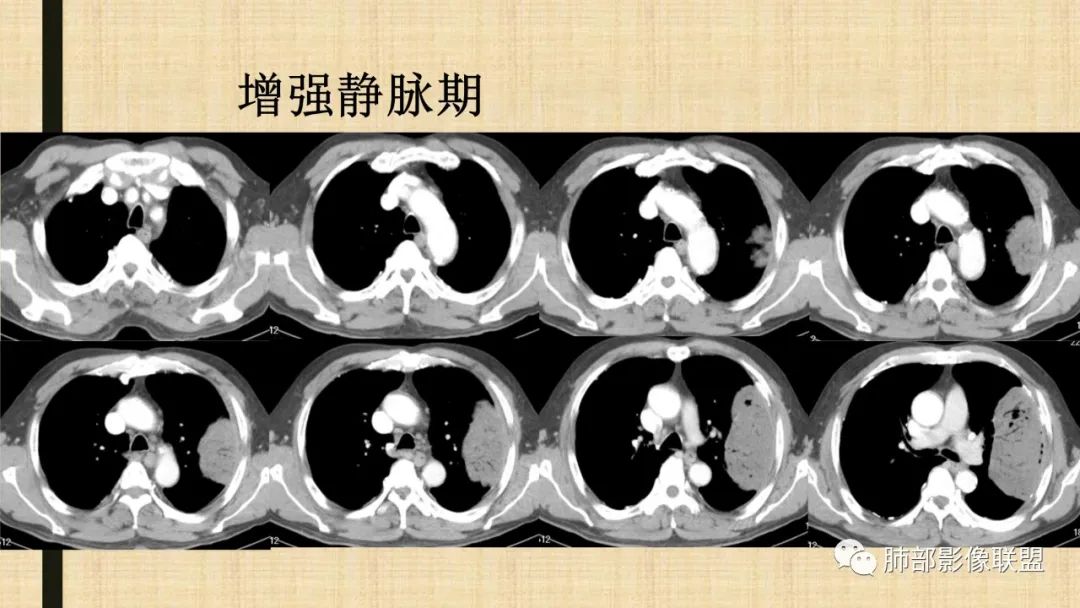

老年男性,糖尿病病史,消瘦、乏力三个月,影像表现左肺上叶胸膜下团块,有一定张力,内部疏松,可见支气管影及坏死区,增强病灶边缘环形强化,内部未见强化,考虑炎性肉芽肿病变,隐球?奴卡?放线菌?鉴别淋巴瘤。

增强没有强化,血管束正常,气管束有正常有扩张,内有空洞,考虑炎性病变,隐球?

支持淋巴瘤,左上肺大肿块,有分叶,边缘光整,病灶内密度不均,可见支气管扩张征,增强后可见血管影征。周围肺野清晰。

左肺上叶肿块,宽基底与胸膜相连,跨叶裂,边缘清晰膨隆,可见小分叶,其内支气管充气,部分扩张、僵直,呈枯枝征,支气管达边征,增强无明显强化,可见血管造影征,考虑恶性病变,淋巴瘤,鉴别粘液腺癌。

我要修正一下观点了:仔细看了视频,肿块占位效应明显,对周围血管,支气管有推挤,增强后强化不明显,NSE增高,半年体重下降25公斤,虽然有内部支气管扩张,血管漂浮,边界清楚支持淋巴瘤,但强化太低,膨隆,占位推挤太明显(淋巴瘤一般没有这么明显的占位效应),胸膜关系有载桩,恶病质明显(乏力,半年体重下降了25公斤),NSE也明显增高,就不支持淋巴瘤了。还是考虑外朝内的恶性肿瘤,间质来源的肉瘤伴有神经内分泌分化或者大神泌。

不支持淋巴瘤的有四点:1、对周围血管支气管推挤明显。2、胸膜有栽桩,3、强化太弱(淋巴瘤一般还是中度以上甚至高度强化多见),4、NSE升高明显,体重下降太明显。

5)肿瘤强化方式:肺部恶性肿瘤强化程度与其血供丰富程度相关,血供丰富多强化明显,反之则较差。由于PSC 周边实性部分富血供及内部黏液变性、坏死,增强后肿块多数呈轻-中度边缘环形强化或不均匀小斑片状强化。国外学者对照病理发现肿瘤细胞或胶原组织增强扫描时强化,无强化的低密度区代表了黏液样变性区和出血坏死区。